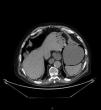

Varón de 82años con distensión y dolor abdominal generalizado, acompañado de vómitos oscuros de aspecto retencionista y deposiciones diarreicas. En radiografía simple de abdomen (fig. 1) existe aire en pared gástrica y dilatación de asas intestinales, por lo que se solicita TC abdominal (fig. 2) donde se observa gas intramural asociado a dilatación gástrica, neumoperitoneo (fig. 3) y gas en vena porta (fig. 4). Se realiza laparotomía exploradora y se observa un estómago distendido con burbujas de gas en su serosa, sin signos de necrosis transmural ni perforación. La gastroscopia intraoperatoria muestra una mucosa necrótica-ulcerada sin sangrado espontáneo en cara posterior, cuerpo y curvatura mayor. Dados estos hallazgos se opta por no realizar ningún acto quirúrgico más. Se aísla Lactobacillus jensenii en hemocultivos y se trata con meropenem+linezolid. El paciente evoluciona favorablemente con mejoría en TC abdominal de control, recibiendo el alta hospitalaria. La gastritis enfisematosa es una patología rara producida por la translocación de microorganismos productores de gas dentro de las paredes gástricas. Hasta en un 42.4%1 de los casos no es posible aislar el causante y conlleva una mortalidad de hasta el 60%2. El TC es la prueba diagnóstica de elección, siendo fundamental el diagnóstico precoz y un tratamiento de soporte vital con antibioterapia de amplio espectro. Se reserva la cirugía cuando existe falta de respuesta al tratamiento conservador, sepsis severa o perforación gástrica3.